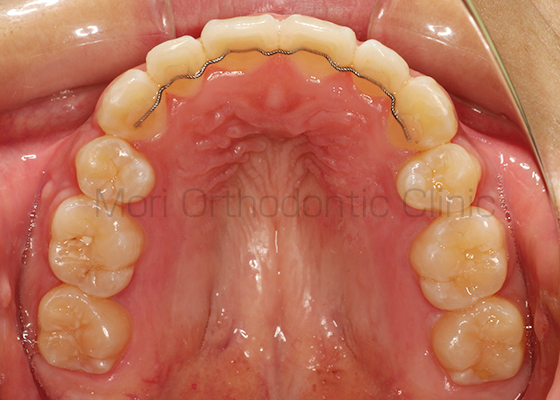

術前

術後

| 主訴 | 歯並び、八重歯 |

|---|---|

| 診断名 | AngleⅡ級叢生 |

| 年齢 | 30歳2か月 |

| 治療装置 | Multi-Bracket(表側矯正)、CARRIERE DISTALIZER |

| 抜歯部位 | 14,24,35,45 |

| 治療期間 | 2年1か月 |

| 治療費 | 825,120円(税込) |

| リスク・副作用 | 矯正治療による歯の移動に伴う痛み、歯根吸収、歯肉退縮、虫歯 |